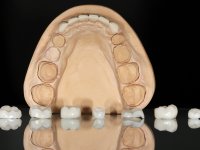

Realizado o diagnóstico e tomada a decisão quanto ao tratamento a executar, tornou-se importante definir qual a sequência de trabalho a adotar no sentido de conseguir a reabilitação da D.V.O. (V.D.O), de forma progressiva e equilibrada. Na primeira fase fez-se uma pré-impressão da arcada inferior com silicone tipo “putty” e em seguida realizou-se o preparo dentário de todo o sector posterior. O preparo para os overlays foi feito coronalmente à linha amelo cementaria no sentido de ser o mais conservador possível. A impressão foi feita com técnica de dupla mistura após afastamento gengival realizado com pasta de caulino. A provisória foi realizada com resina composta de polimerização dual. Em laboratório foram realizados os overlays após se ter aberto ligeiramente (1,5mm) a D.V.O. nos modelos montados em articulador semi-ajustável. Simultaneamente o sector antero-inferior foi encerado no sentido de acompanhar este aumento da D.V.O. Também foi confecionada uma chave de silicone translucido para posterior confeção dos provisórios antero-inferiores. Em boca foi primeiro realizada a provisionalização dos dentes anteriores utilizando resina composta previamente aquecida após preparação das superfícies dentárias para a adesão. Foi colocado o dique de borracha para promover o isolamento absoluto e posteriormente foram colados os overlays. Em laboratório foi realizada nova chave de silicone para confecionar os provisórios antero-superiores. Seguidamente em boca foram preparados os seis dentes antero-superiores após colocação do fio de afastamento gengival. Feita a preparação adequada das superfícies dentárias foi realizada a impressão com técnica de dupla mistura e a respetiva provisória. Em laboratório foram confecionadas 6 facetas feldespáticas num modelo de trabalho tipo “Geller”. A provisória foi removida e as facetas foram coladas em boca utilizando um isolamento relativo competente. Esta opção foi tomada em virtude de uma prévia experiencia negativa com a colocação do dique de borracha na mandibula. Após a colagem dos laminados antero-superiores foram dadas 12 semanas para avaliar a adaptação do paciente à nova situação e então iniciar a confeção das facetas antero-inferiores. Após colocação do fio de afastamento gengival. foram feitos os preparos dentários adequados e em seguida foi feita a impressão. Também foi feita a preparação do dente 3.4 que, entretanto, tinha sofrido uma fratura do overlay. As facetas e a restauração do 3.4 foram realizadas num modelo de trabalho tipo “Geller”. Após remoção da provisória, as facetas foram coladas em boca, utilizando um isolamento relativo pelas razões apontadas anteriormente. Após colocação do trabalho o paciente foi reabilitado por outros colegas com um implante na zona do 2.6 e substituição da coroa aparafusada sobre o implante colocado no local do 3.5. Posteriormente surgiram fraturas nos overlays dos dentes 4.7 e 3.7 que foram reabilitados com overlays em Zr.